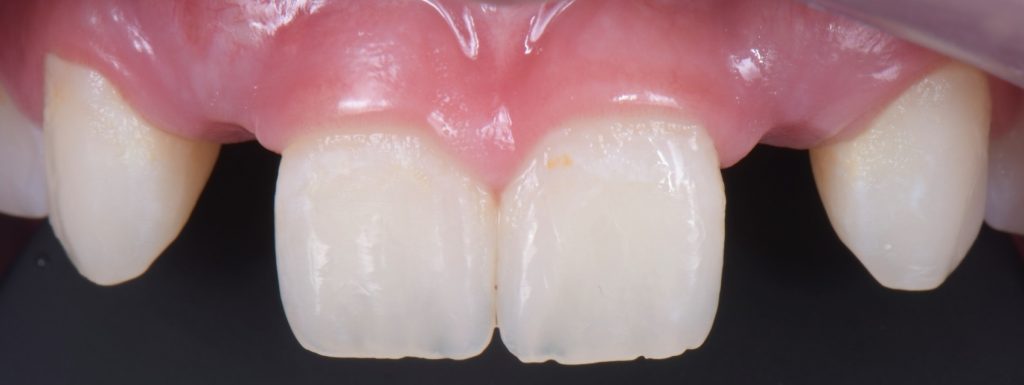

Solution #2: Resin-Bonded Fixed Dental Prostheses (RBFDP)

RBFDP is a proven solution for congenitally missing lateral incisors (Figs. 2-12). Although it is considered an interim restoration, the literature provides substantial evidence supporting its long-term potential. However, the clinical performance of an RBFDP is significantly superior to that of a bilateral retainer, and the dissimilar mobility of the abutment teeth explains this.

From an occlusal standpoint, patients with shallow overbites or a large amount of overjet make better candidates for RBFDP, and the pontics should be avoided in all lateral excursions, including crossover.

The amount of tooth reduction is based on available interocclusal space, and often, there is enough space requiring minimal preparation. The key is to stay in enamel. It is also advisable to stay 2.0 mm away from the incisal edge so that the zirconia retainer does not affect the translucency of the natural tooth.

If the patient has a deep overbite, proclined teeth, or mobile abutment teeth, an RBFPD may not be the best treatment option. This is why they are often used as a long-term provisional until the patient is old enough to have an implant placed.